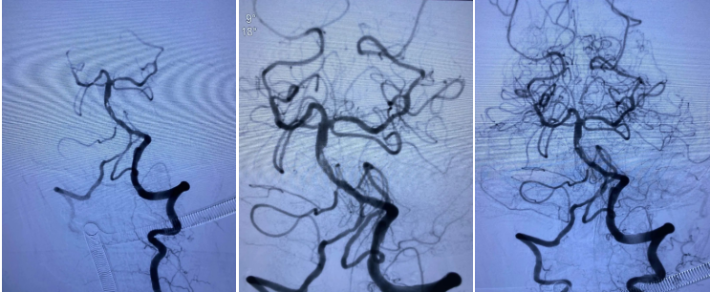

造影未见出血,血流良好,原狭窄在第一次支架时球囊扩张,现在狭窄已缓解。狭窄远端血管内膜稍不光滑。观察30min,血流稳定,为避免再放支架血栓,同时本次预后尚未知,暂不植入第二枚支撑支架,予以替罗非班注射液应用。

术后CT未见出血,期待良好预后。